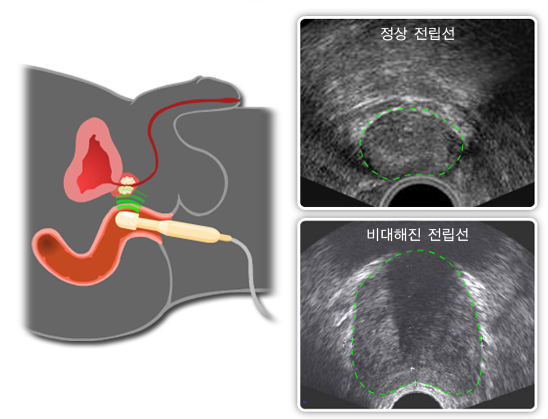

전립선은 남성의 정액 일부를 생성하는 밤톨만한 작은 크기의 중요한 생식 기관 중 하나이며 나이가 들면서 점점 크기가 커진다. 전립선은 방광 아래에 위치해 있으며 요도를 둘러싸고 있다.

- 초음파 : 항문을 통해 초음파 장치를 삽입하여 촬영, 전립선의 모양과 크기, 주변 조직 확인